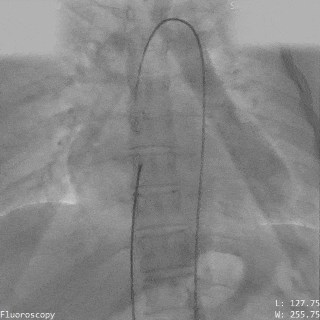

轨道建立

导丝通过主动脉窦瘤破口

导丝置于下腔静脉

圈套器抓取导丝建立完整轨道